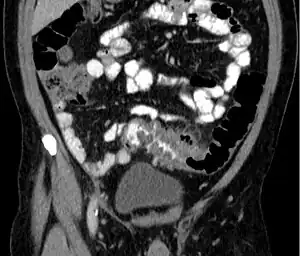

People with the above symptoms are commonly studied with computed tomography, or CT scan.[13] The CT scan is very accurate (98%) in diagnosing diverticulitis. In order to extract the most information possible about the person's condition, thin section (5 mm) transverse images are obtained through the entire abdomen and pelvis after oral and intravascular contrast have been administered. Images reveal localized colon wall thickening, with inflammation extending into the fat surrounding the colon.[14] The diagnosis of acute diverticulitis is made confidently when the involved segment contains diverticula.[15] CT may also identify people with more complicated diverticulitis, such as those with an associated abscess. It may even allow for radiologically guided drainage of an associated abscess, sparing a person from immediate surgical intervention.

Diverticulitis on CT scan in coronal view -